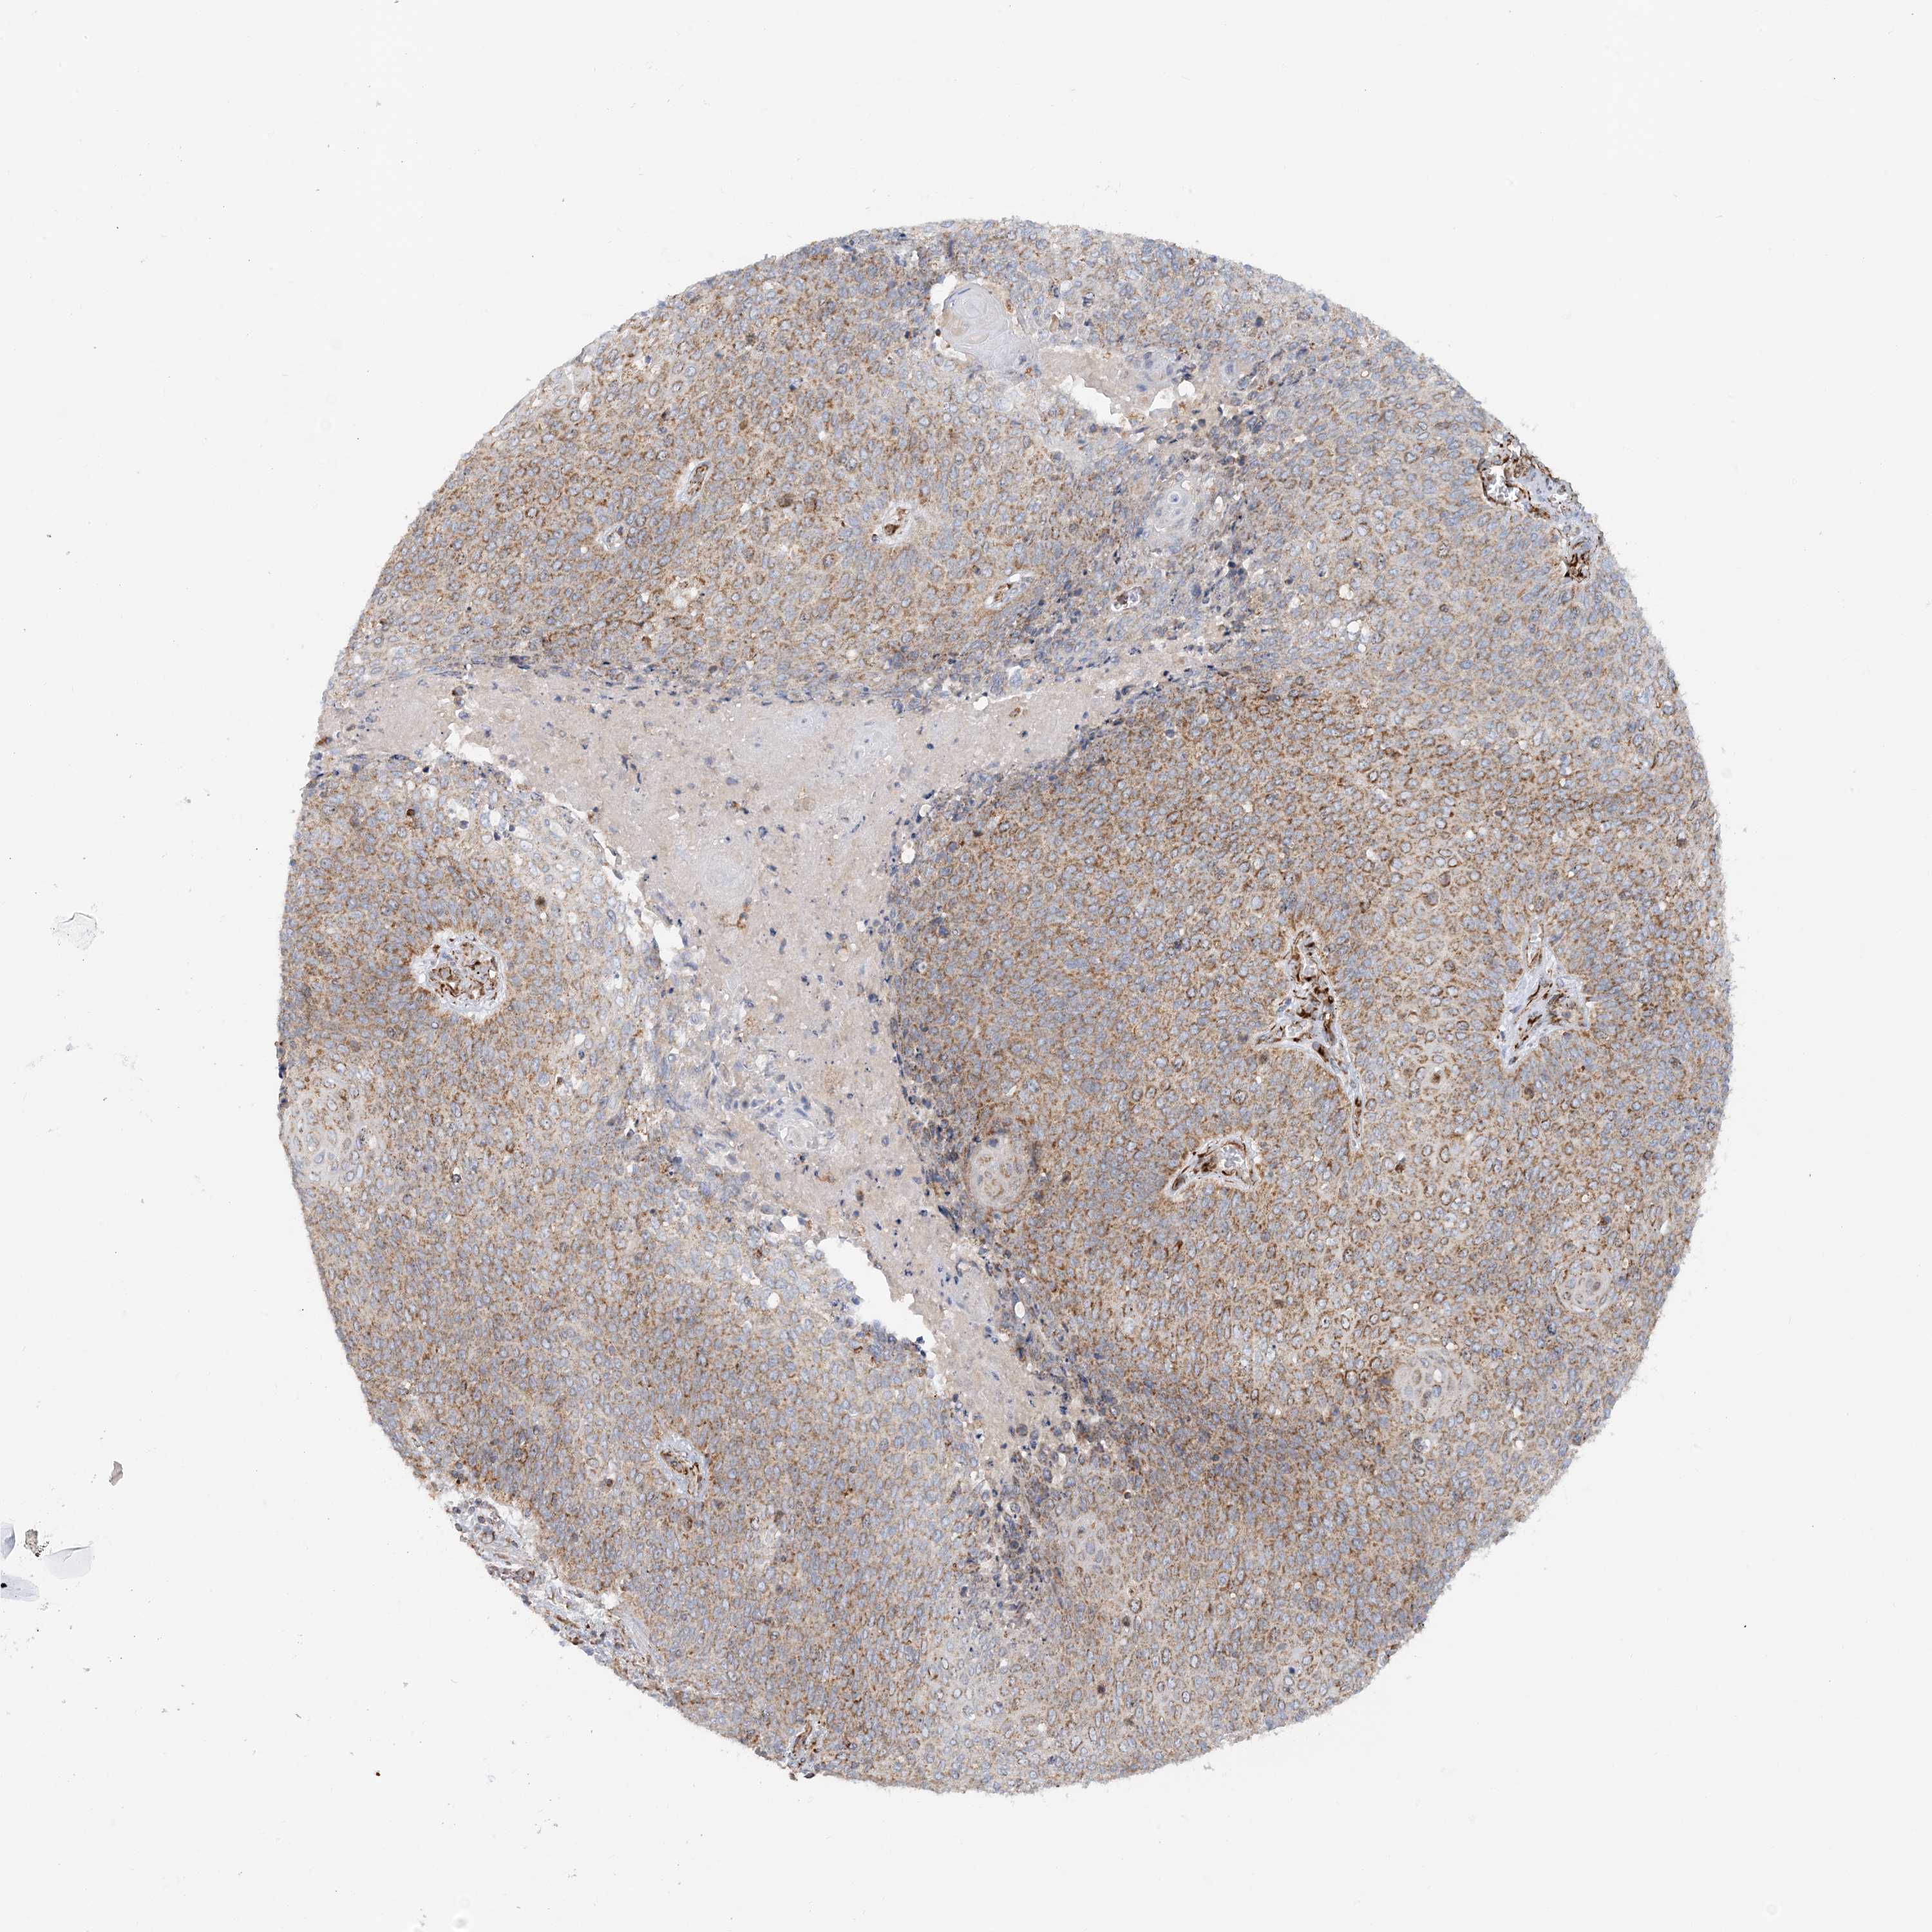

CERVICAL CANCER - Protein expressioni

A mouse-over function shows sample information and annotation data. Click on an image to view it in a full screen mode. Samples can be filtered based on level of antibody staining by selecting one or several of the following categories: high, medium, low and not detected. The assay and annotation is described here.

Note that samples used for immunohistochemistry by the Human Protein Atlas do not correspond to samples in the TCGA dataset.

Antibody stainingi

Antibody staining in the annotated cell types in the current human tissue is reported as not detected, low, medium, or high, based on conventional immunohistochemistry profiling in selected tissues. This score is based on the combination of the staining intensity and fraction of stained cells.

Each image is clickable and will lead to virtual microscopy that enables deeper exploration of all samples and also displays staining intensity scores, fraction scores and subcellular localization as well as patient and tissue information for each sample.

Antibody HPA031966

Staining

High

Medium

Low

Not detected

Intensity

Strong

Moderate

Weak

Negative

Quantity

>75%

75%-25%

<25%

None

Location

Nuclear

Cytoplasmic/membranous

Cytoplasmic/membranous,nuclear

Squamous cell carcinoma, NOS

Adenocarcinoma, NOS